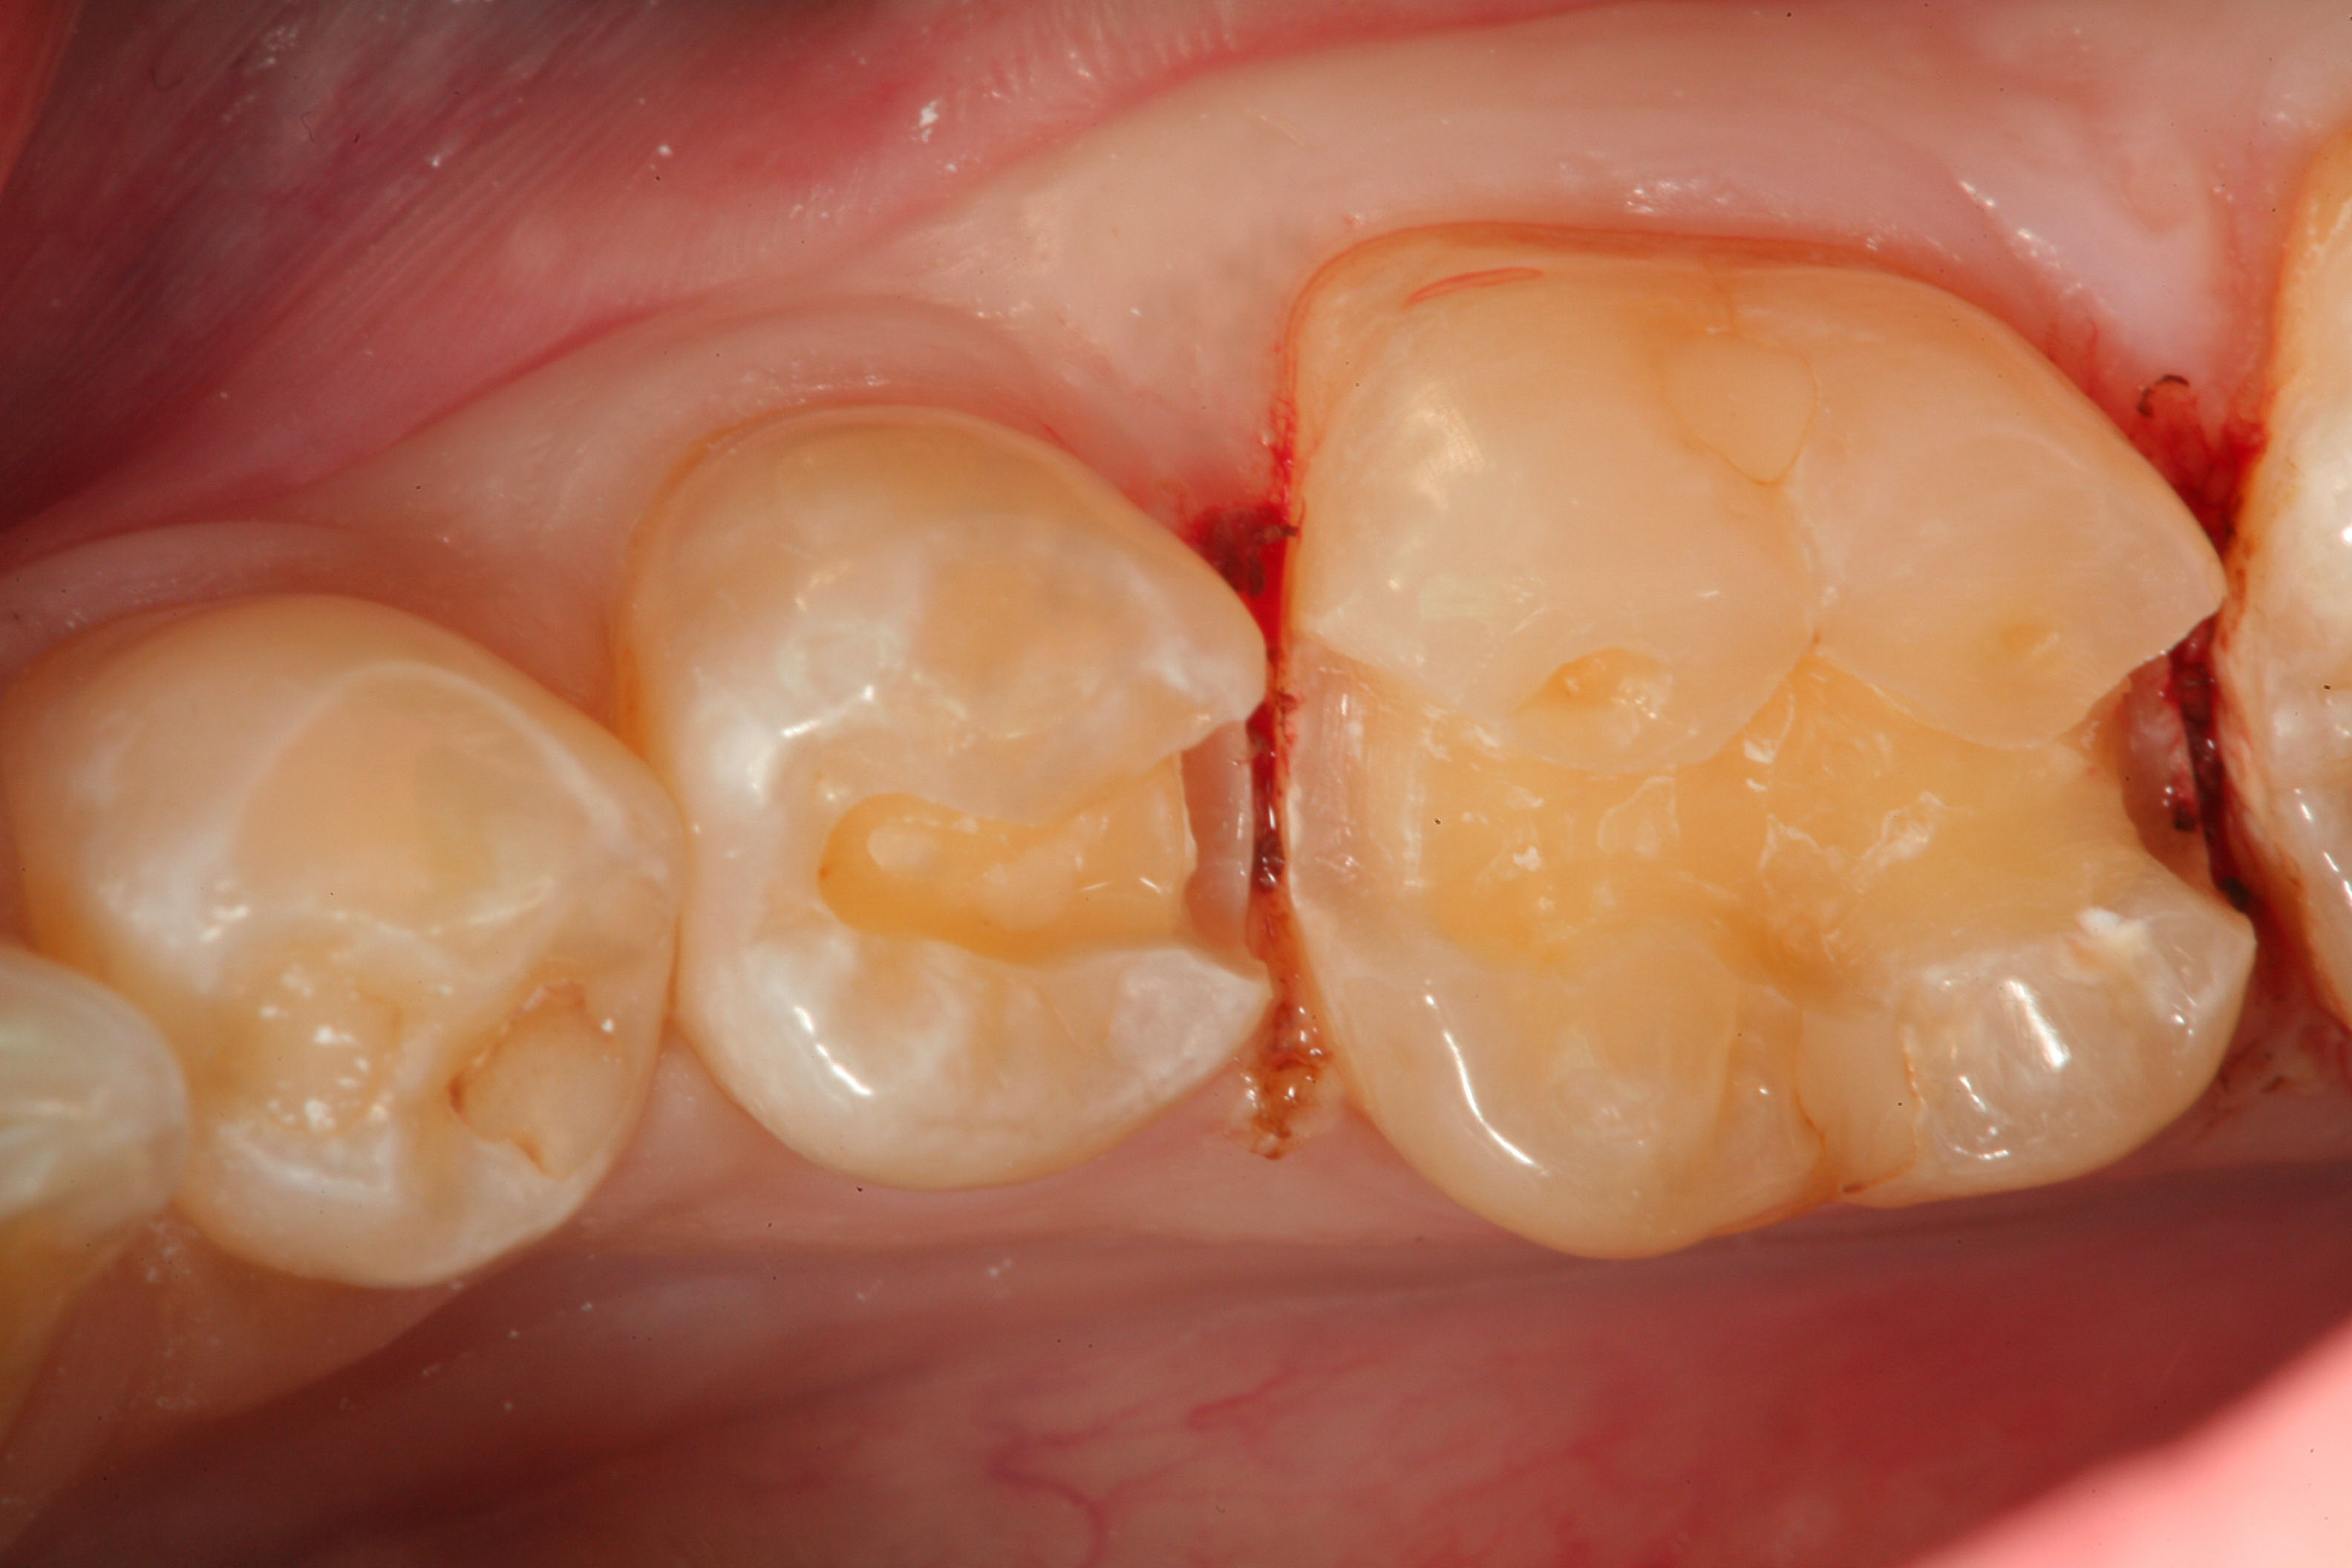

Fig 7. After slot preparation in the distal marginal ridge of tooth No. 5, proximal decalcification and decay at the dentino-enamel junction is clearly seen, although this lesion was not fully visible on radiographic examination.

Figure 7

Fig 8. After isolation, a sectional matrix is placed to restore contact and proximal anatomic form to the composite to be placed. The goal is to perform as little rotary finishing and polishing as possible by having the matrix fit precisely to the cavity margins.

Figure 8

Fig 9. A self-etching bonding resin is scrubbed into the cavity preparation, air-thinned, and then light-cured according to manufacturer’s instructions.

Figure 9

Fig 10. A Giomer bulk-fill flowable is used for this conservative slot preparation so that the entire cavity can be filled with one increment even though the depth of the proximal box is approximately 4 mm.

Figure 10

Fig 11. An occlusal view of the completed distal-occlusal Giomer composite restoration on tooth No. 5.

Figure 11